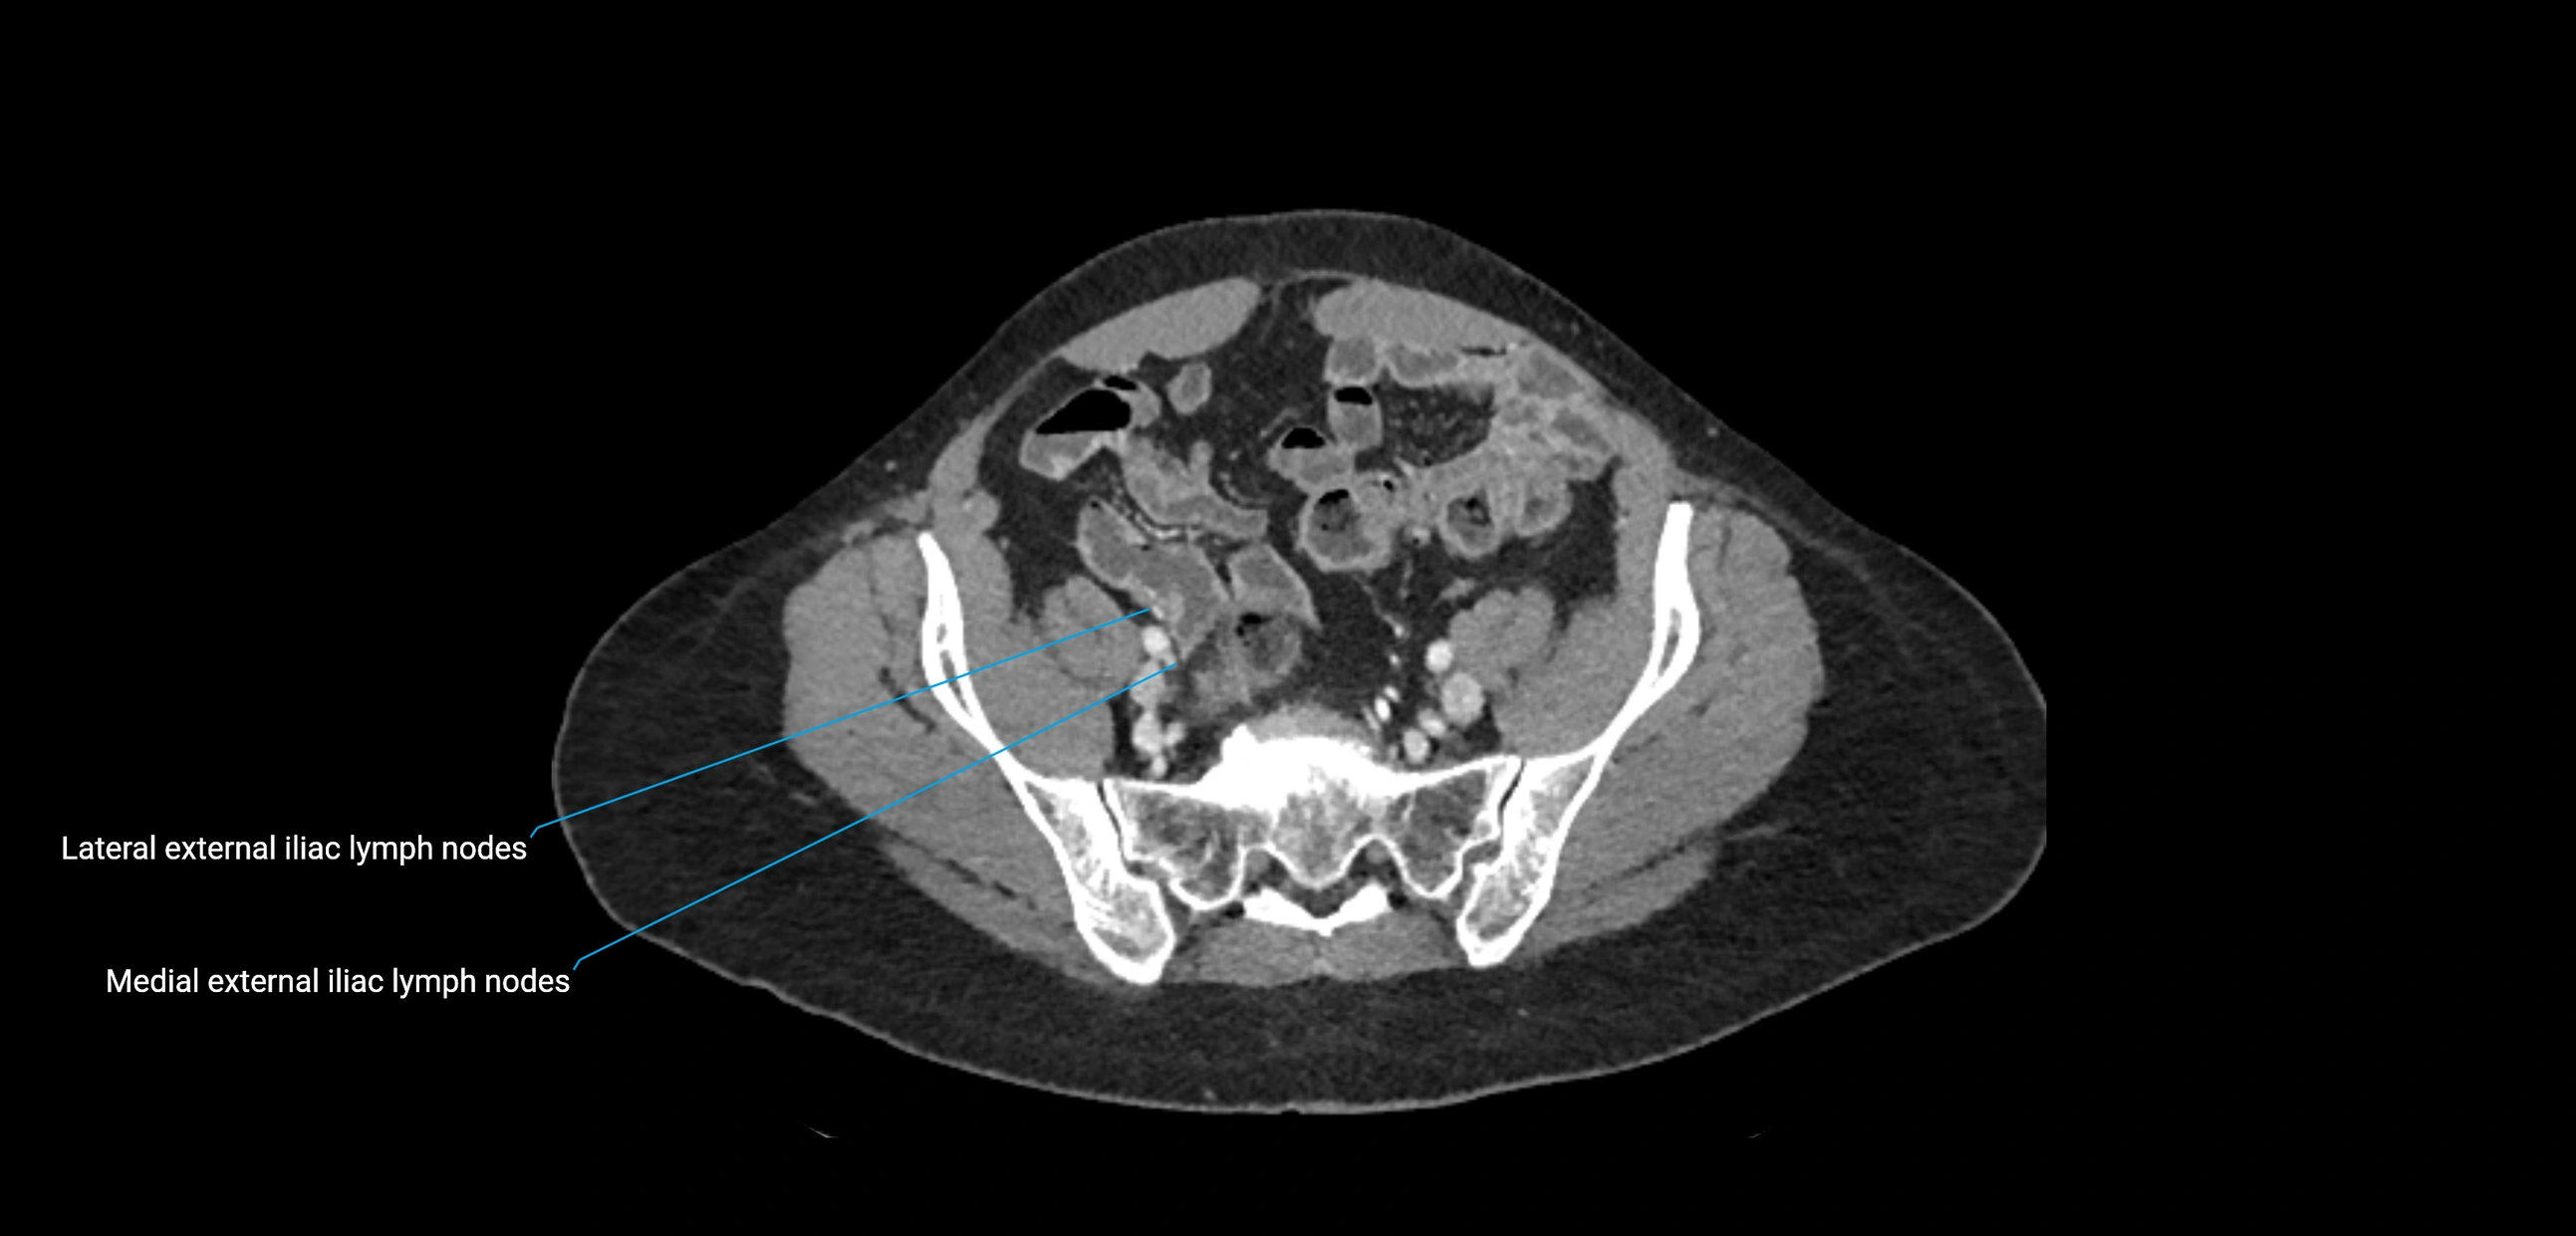

CT Appearance

CT Pre-Contrast:

• Nodes appear as soft-tissue density nodules adjacent to the aorta and IVC

CT Post-Contrast:

• Normal nodes enhance homogeneously

• Malignant nodes may show heterogeneous enhancement, central necrosis, or conglomerate formation

• Size >1 cm short axis is suspicious, though morphology and distribution are equally important